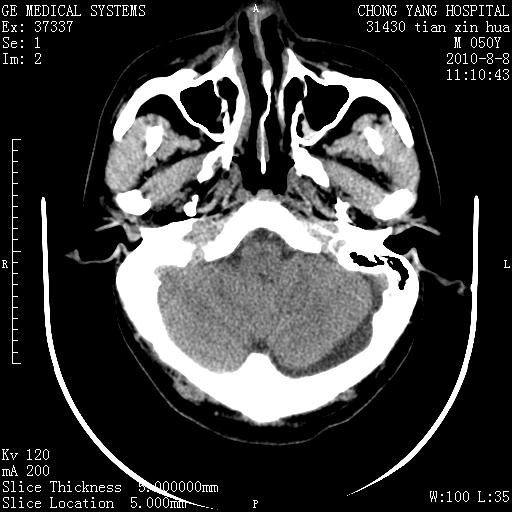

标题: CT28268:M50Y 头部外伤。 [打印本页]

标题: CT28268:M50Y 头部外伤。

考虑左侧枕部硬膜下积液。

乙状窦增宽,蛛网膜囊肿不除外

考虑左侧枕部蛛网膜囊肿;建议行mri检查。

病灶两端有脑膜尾征,考虑蛛网膜囊肿

枕骨稍变薄,脑组织有受压。首先考虑蛛网膜囊肿。